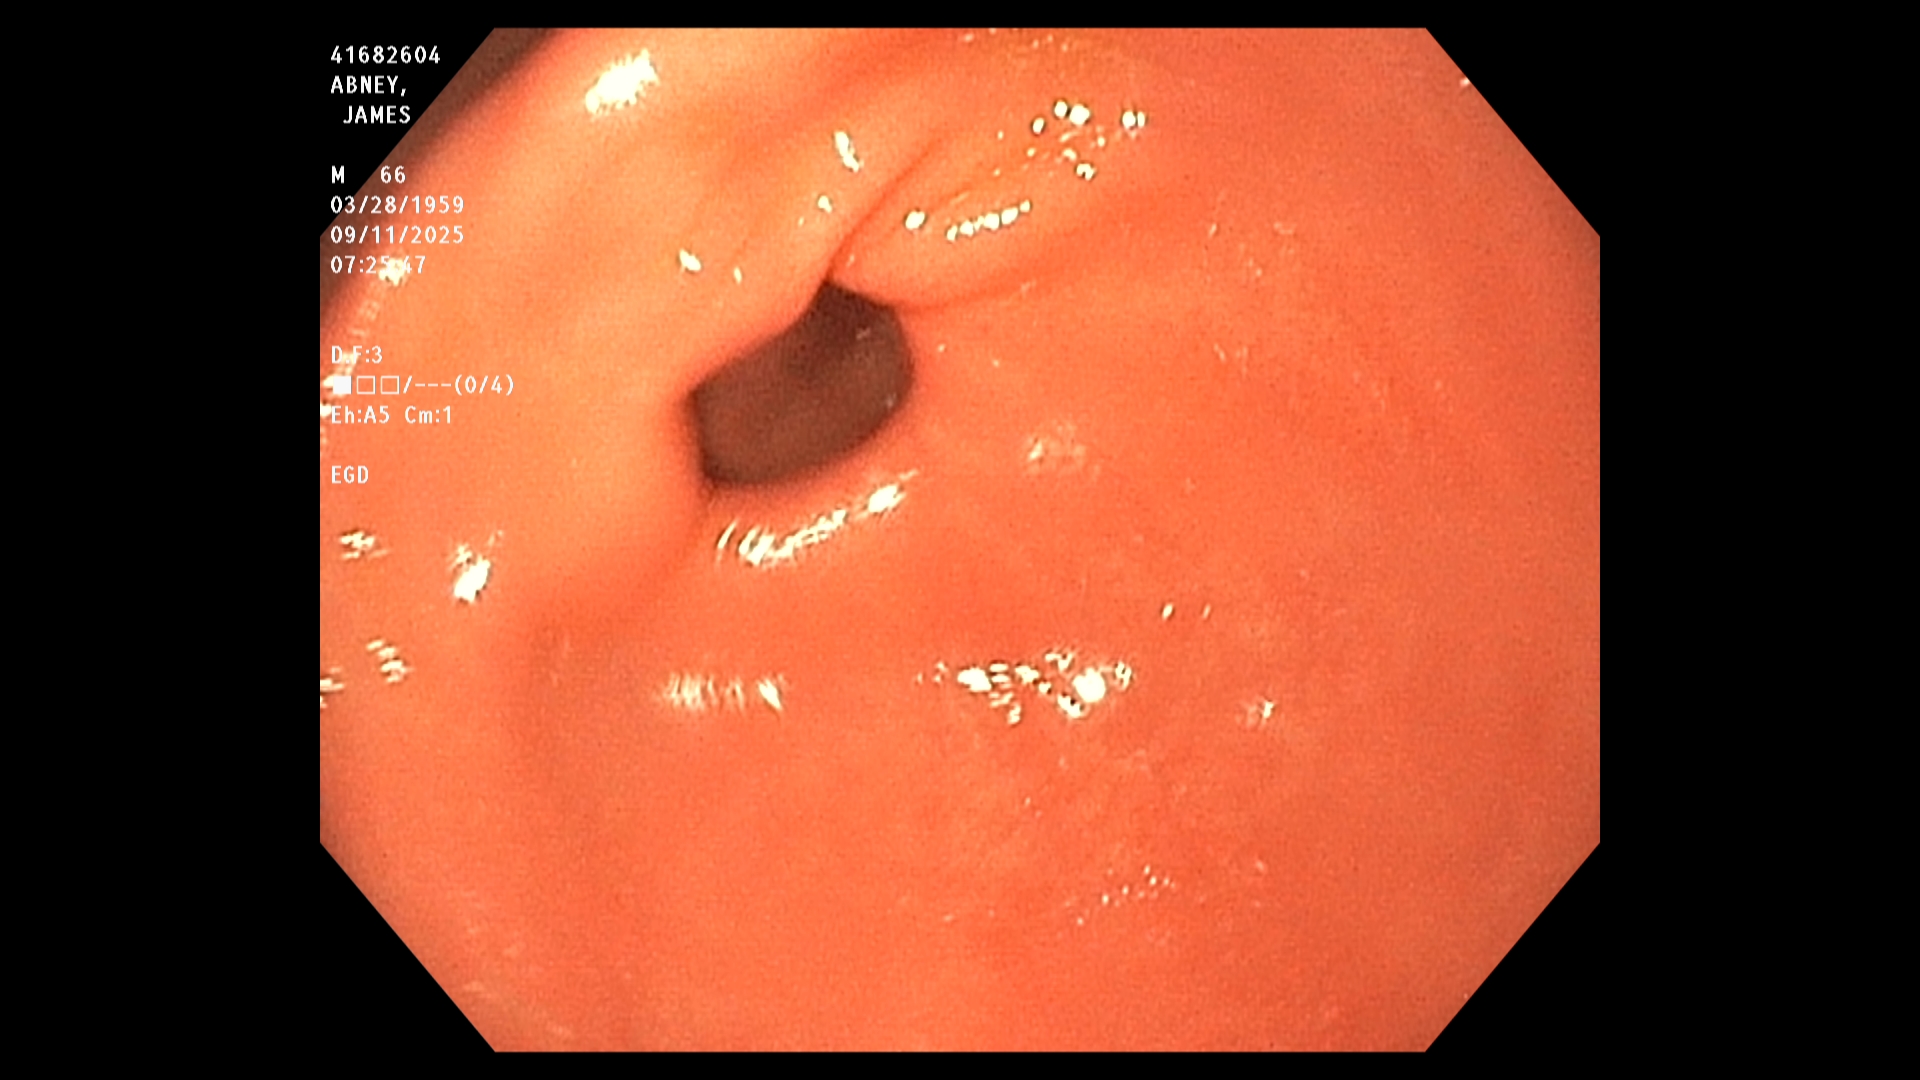

The endoscopist in this study generated a series of images showing the stomach, duodenum,

duodenal bulb, and esophagus, among others. The stomach was imaged first. The image is a

retroflexed view, in which the endoscope was passed through the stomach and the camera

turned backward to take the image, which shows both the stomach and an upstream portion of

the endoscope. The endoscope was next passed into the duodenum, farther down the GI tract,

and then withdrawn while care was taken to observe mucosal detail.